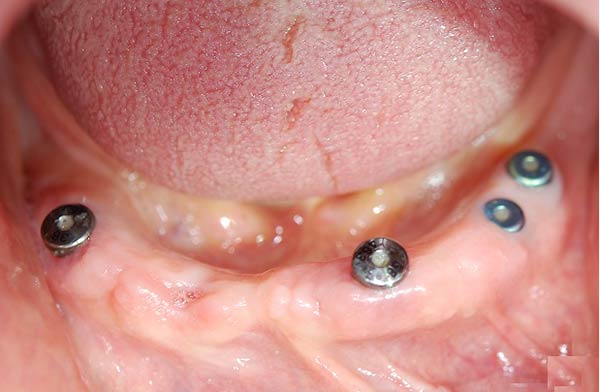

Protesi totale con mesostruttura avvitata su 5 impianti in un paziente edentulo